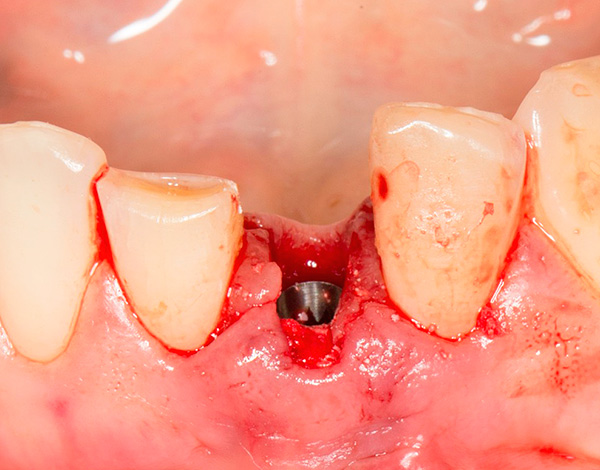

A foto abaixo mostra os implantes removidos da mandíbula:

Nas pequenas situações em que, por alguns motivos, dependendo ou não do médico, os implantes instalados na mandíbula são rejeitados, ocorre uma diminuição banal no tecido ósseo. Essa diminuição óssea no futuro pode ser facilmente compensada por sua restauração artificial usando um enxerto ósseo.